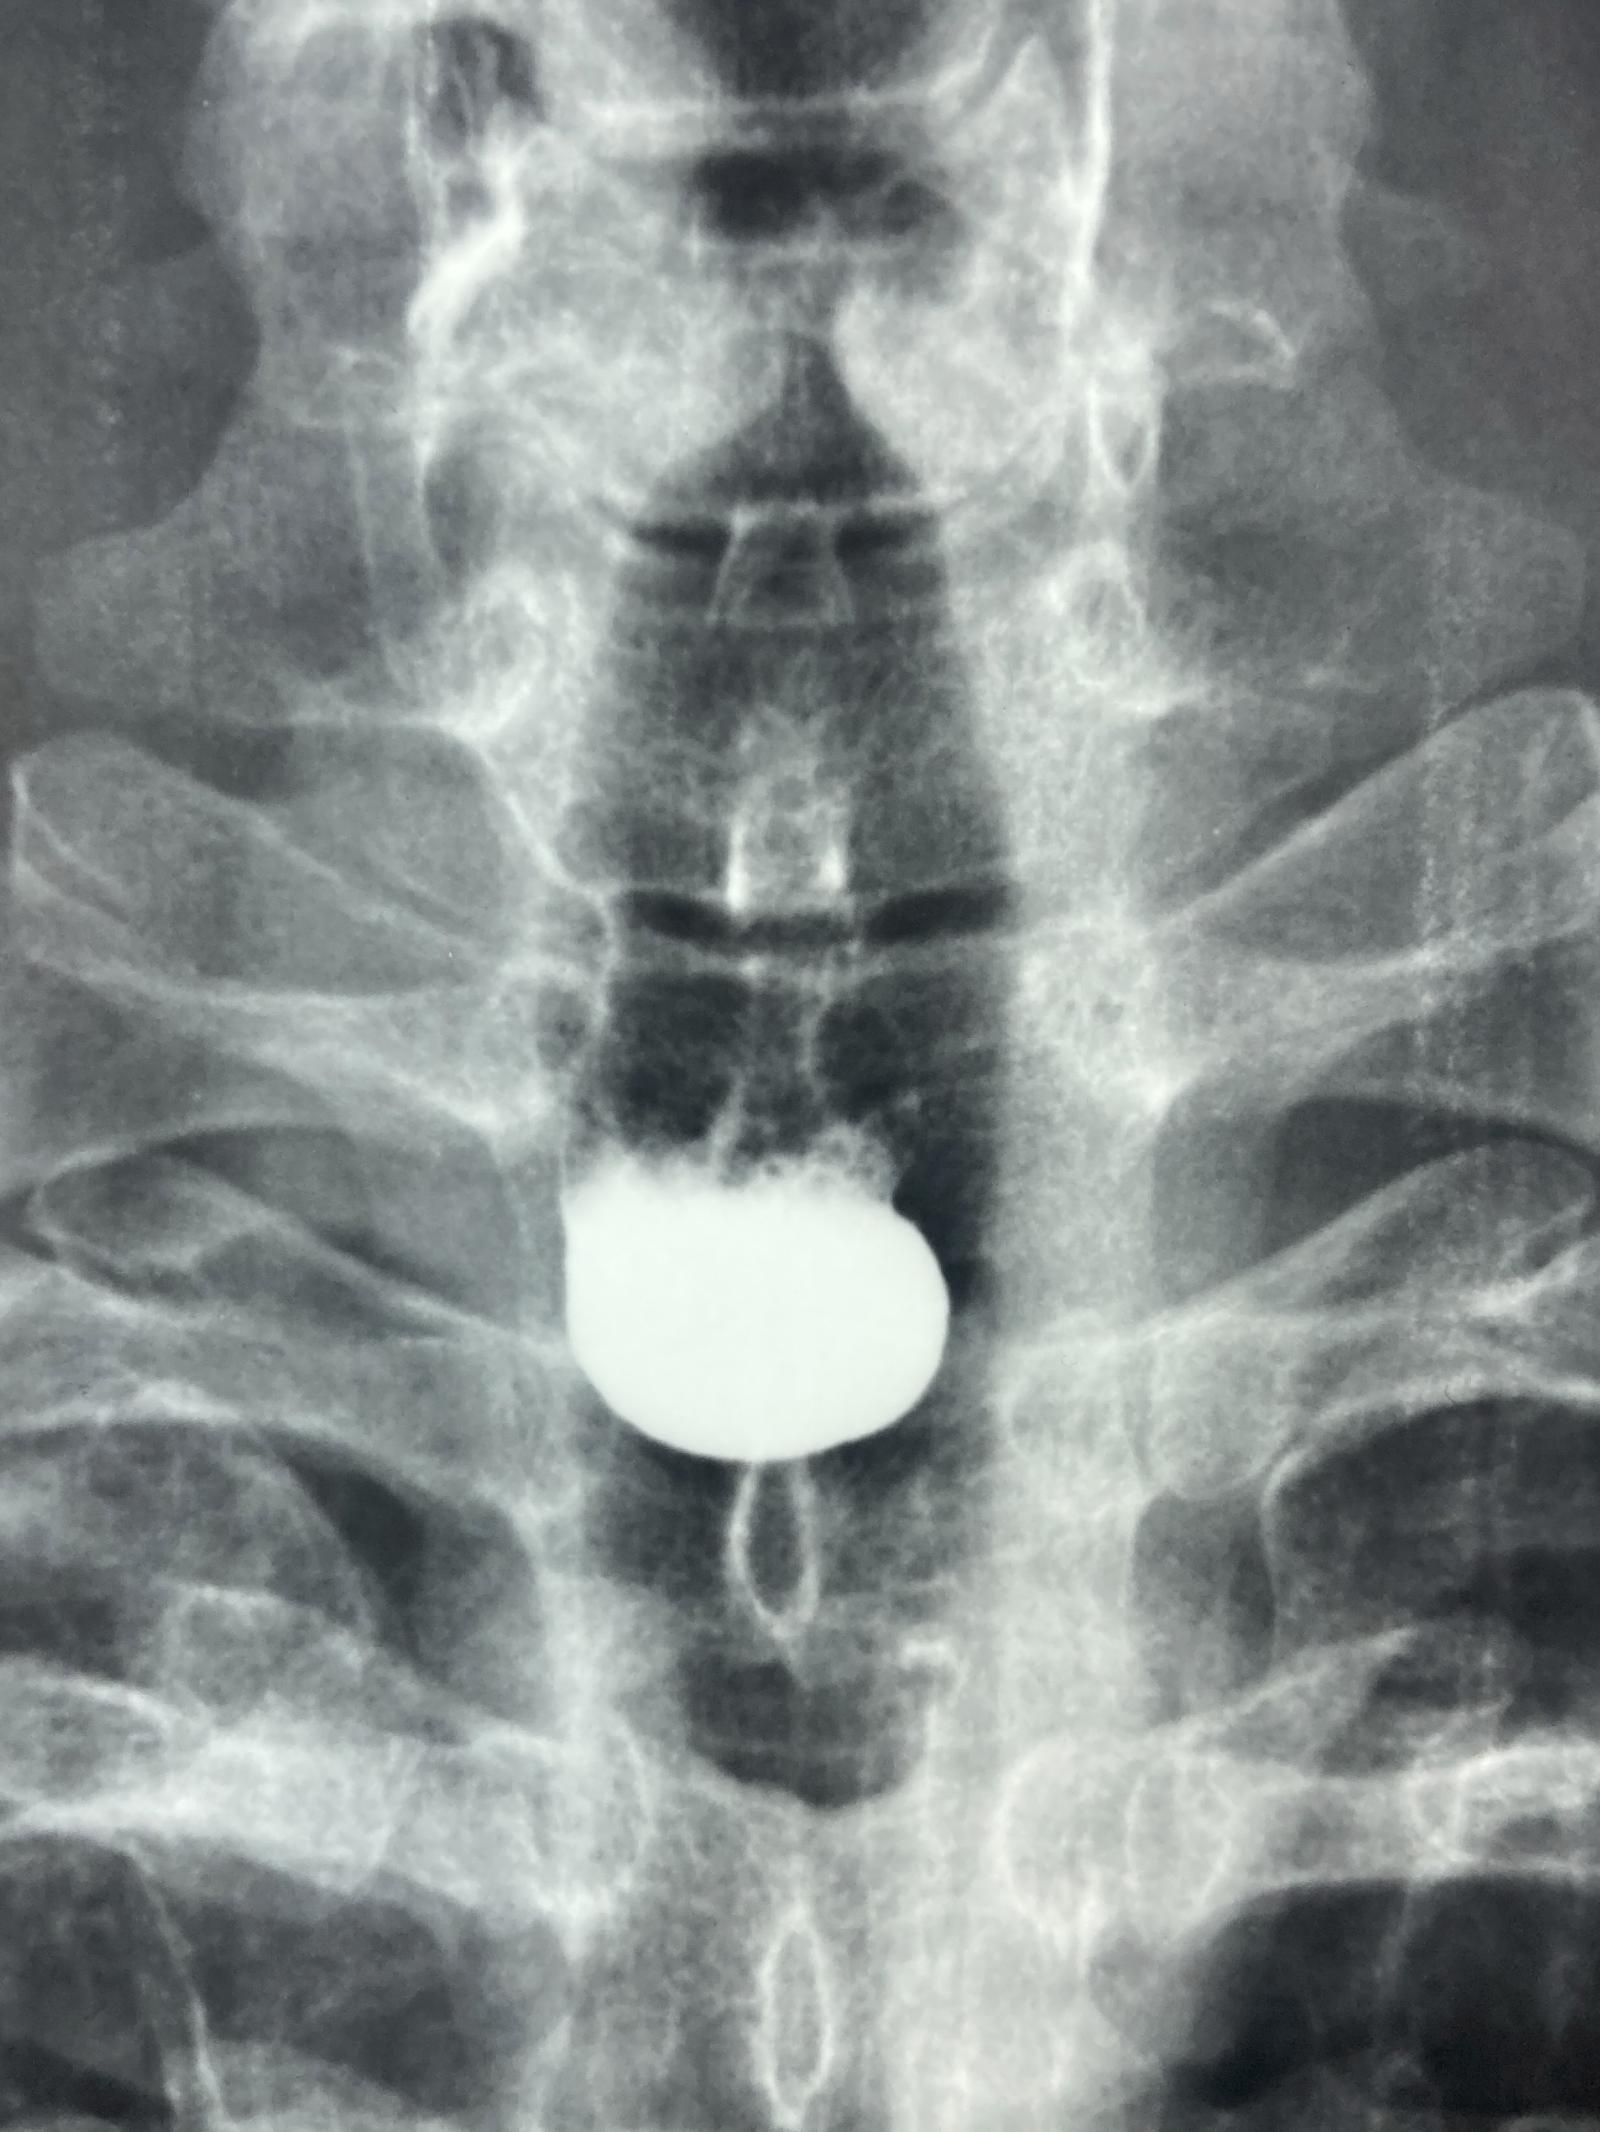

Caso Código 251B de Divertículo de Zenker - Case Code 251B of Zenker's Diverticulum

Rx contrastado do esôfago revelando divertículo faringoesofágico de Zenker.